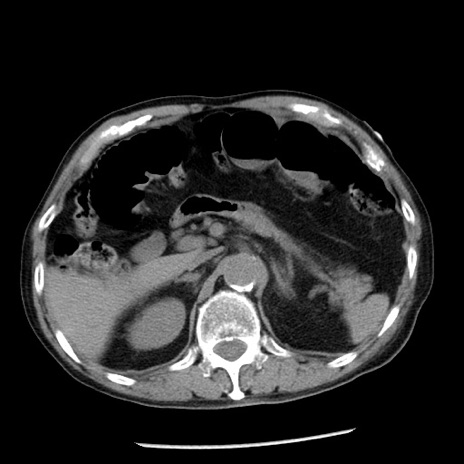

症例26(横断像)

【症例】80歳代男性

【主訴】嘔吐

【現病歴】昨晩2回嘔吐あり、今朝になっても嘔吐あり。来院。

【既往歴】胃潰瘍

【身体所見】意識清明、BT 37.6℃、BP 166/95mmHg、HR 100bpm、SpO2 97%、腹部:平坦・軟、腸蠕動音聴取良好、圧痛なし。

【データ】WBC 21900、CRP 1.46